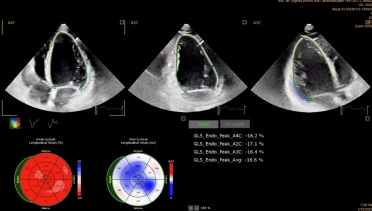

TTE was performed. The LV had a normal size, however, left ventricular ejection fraction (LVEF) was mildly impaired (48%) with mild longitudinal dysfunction (GLS -16,6%). The mitral valve appeared thickened and redundant, with bi-leaflet prolapse and mild regurgitation. MAD was seen, with a length of 4-5mm measured in mid-systole.

Tissue Doppler imaging (TDI) of the lateral wall revealed a second systolic peak, with a velocity of 17cm/s. Through speckle-tracking analysis, a double peak strain pattern is seen on the basal infero-lateral wall (orange arrows).